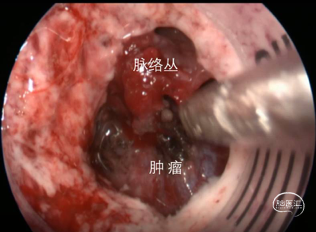

【暴露肿瘤】

【观察肿瘤】

【切除肿瘤】

【切除后观察】